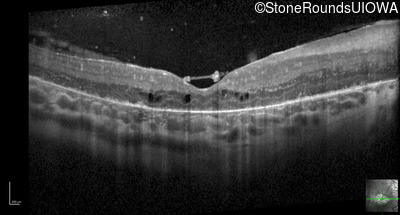

Optical Coherence Tomography - Right - 20/160

Exemplar / OCT Stack